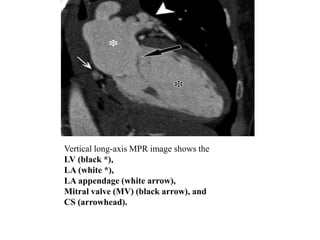

Vertical Long-Axis View:- is a parasagittal plane oriented along the

long axis of the LV lumen.

The relationship between the left atrium (LA) and the LV is assessed

on vertical long-axis images.

The inferior and anterior walls of the LV myocardium are optimized on

this view.

The structure and function of the bicuspid MV and LV are well

demonstrated on vertical long-axis cine images, and the LA appendage

and CS are routinely depicted.

Vertical long-axis MPR image shows the

LV (black *),

LA (white *),

LA appendage (white arrow),

Mitral valve (MV) (black arrow), and

CS (arrowhead).